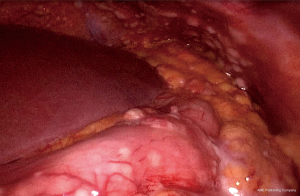

A 62-year-old gentleman was admitted in the Second Affiliated Hospital of Zhejiang University, School of Medicine, with a 20-day history of worsening weakness and poor appetite. This was associated with discomfort of the right flank, hard stools and a loss of weight of 5 kg over one month. No nausea, vomiting or fever were reported. The patient had no history of renal disease. Physical examination on admission revealed BMI of 24.2 (a height of 172 cm and a weight of 71.6 kg). Left cervical lymph nodes were not palpable. Mild tenderness was present in the epigastric region. Gastroscopy showed a huge annular irregular mass on the wall of lower two thirds of the gastric body with peripheral mucosa edema (Figure 1). Biopsy confirmed the presence of a low-grade adenocarcinoma. Abdominal enhanced CT scan revealed a large-scale thickness (size of 9 cm) of the gastric wall with serosa invasion, infiltration of the left lower ureter, multiple enlarged perigastric lymph nodes (lymph nodes No. 2, 4, 5, 6), suspicious metastatic nodes in greater omentum, and a small amount of pelvic effusion (Figure 2). Furthermore, 18F-fluorodeoxyglucose (FDG) PET/CT scan showed that diffuse enhancement in the stomach (SUVmax =6.72), perigastric lymph nodes (SUVmax =4.22), a blurry omentum and a small amount of pelvic effusion (Figure 2).